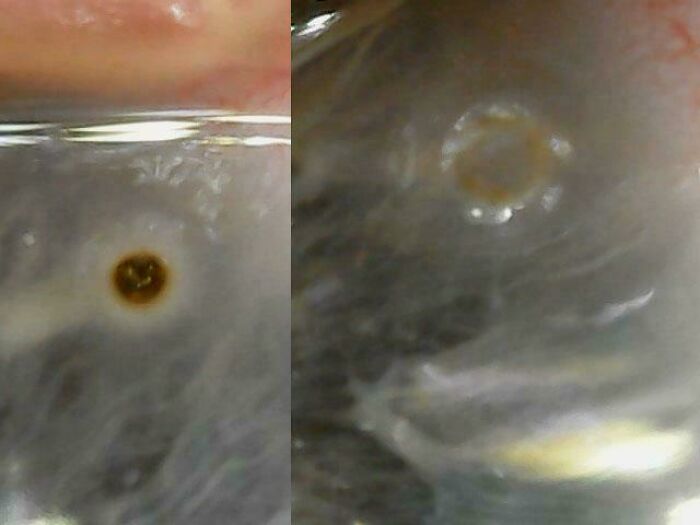

Super Rare: Scleromalacia Perforans Case Revealed